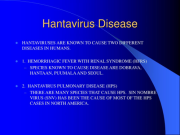

| 13:06, 17 במרץ 2024 | Hanta 2.png (קובץ) |  |

165 קילו־בייטים | Motyk | 1 | |

| 13:02, 17 במרץ 2024 | Hanta 1.png (קובץ) |  |

224 קילו־בייטים | Motyk | 1 | |